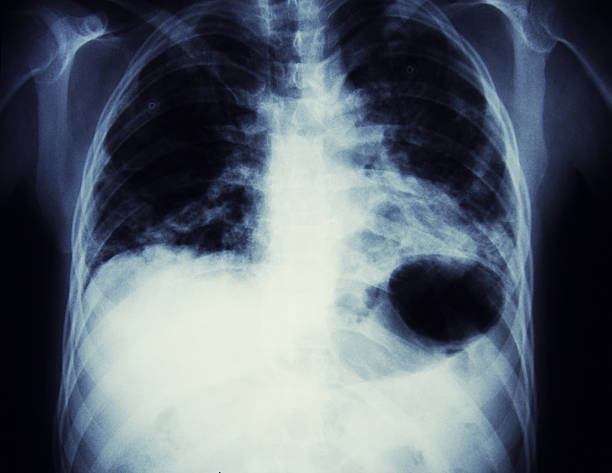

폐암의 초기 증상 5. 객혈

객혈은 또한 폐암의 초기 증상입니다. 암세포가 작아도 기관지를 관통하면 암세포 주변에 수많은 혈관이 생긴다. 폐가 기관지를 자주 자극하면 기침과 가래가 자주 발생하기 때문에 대부분의 폐암 환자들이 통증을 호소하는 것으로 알려져 있다.